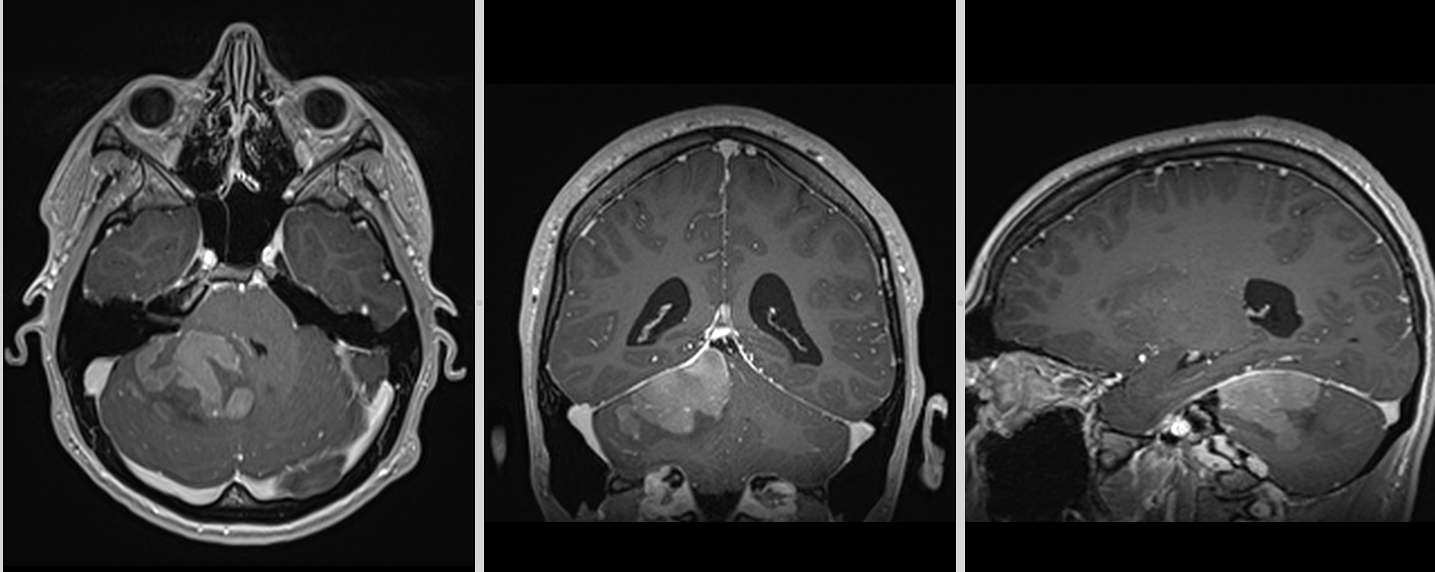

RMN cerebral

Este investigația de elecție. Meduloblastomul apare de obicei ca:

- leziune solidă, bine delimitată sau infiltrativă

- hipointensă T1, hiperintensă T2

- captare intensă de contrast

- posibilă restricție de difuzie (densitate celulară mare)

La adult, localizarea în emisfera cerebeloasă poate duce la confuzie cu alte tumori (metastaze, hemangioblastom, astrocitom).

RMN spinal

Este obligatoriu pentru evaluarea diseminării în LCR.